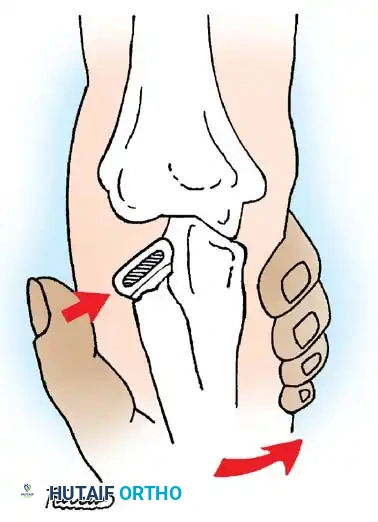

The Patterson Technique (Modified by Neher and Torch)

Fig. 33-42 Reduction technique for radial neck fractures.

- Positioning: The patient is placed supine. An assistant firmly stabilizes the distal humerus and the radius distal to the fracture site.

- Maneuver: With the elbow in full extension, the surgeon applies a strong varus stress to the elbow with one hand. This opens the radiocapitellar joint laterally.

- Reduction: Using the thumb of the opposite hand, direct lateral-to-medial pressure is applied over the tilted radial head to lever it back into anatomical alignment.

- Immobilization: The forearm is then placed in 90 degrees of flexion and pronation to lock the reduction.